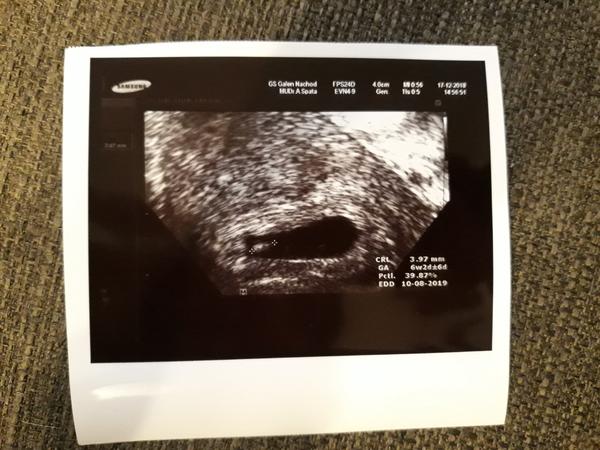

Velikost plodu v 6+0

Holky, tak jsem dnes byla na kontrole. Jsem přesně 6+0 a už krásně tlouklo srdíčko 🙂 Prcek je veliký prý necelých 5 mm. Není to málo?

Myslim, ze neni. Ja byla na kontrole taky kolem toho 6tt a meli jsme 3mm

@slunicko1551 není já jsem měla taky pět mm a byla jsem 6+2 a taky srdíčko jako zvon

Já měla v 6+5 kolem 7mm. Moje Dr a hlavně sestřička říkala, nic nehledat na internetu 😂😂😂. Pokud budu mít nějaký dotaz tak si klidne zavolat.